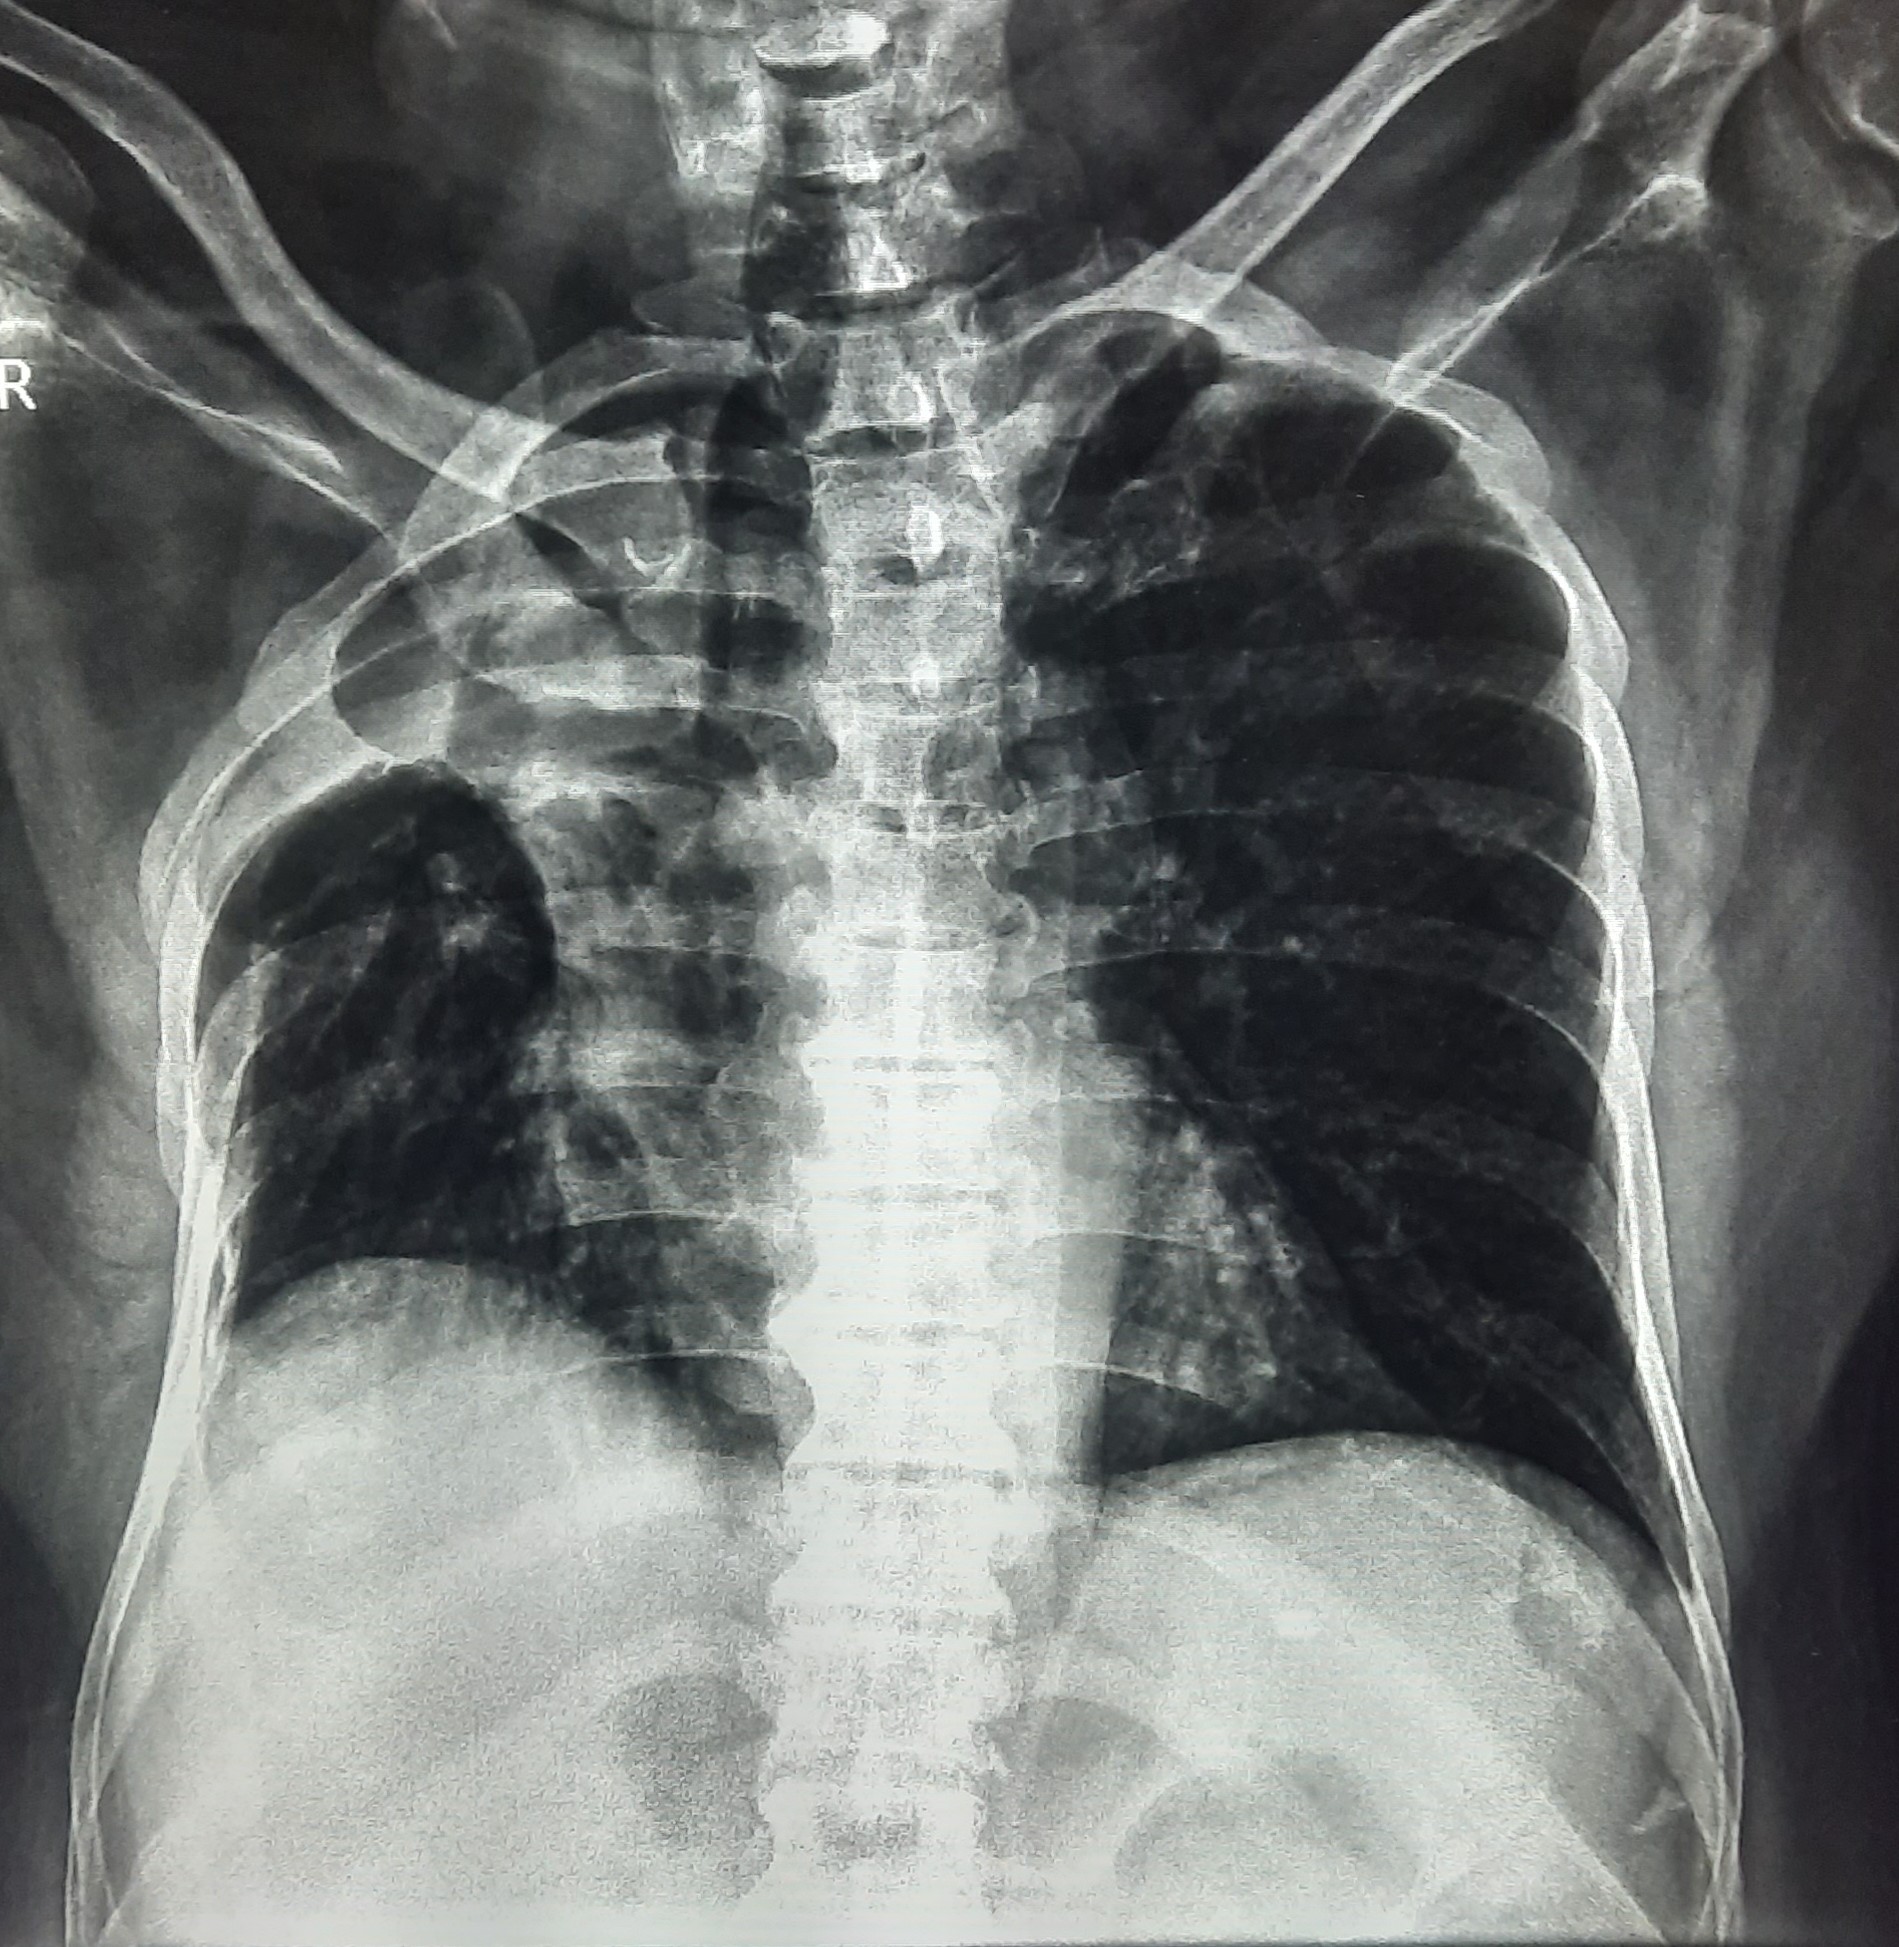

| 51 | IGGMC, Nagpur, Nagpur | P2 | 29-4421 | Santosh Neware | Consent taken on Paper | 40 Yrs. |

Provisional Diag : Pulmonary Tuberculosis

Final Diag : Pulmonary tuberculosis (Microbiologically Confirmed PTB) |

TB Case (Confirmed) | Right Upper & mid zone fibro cavitary lesion present, upward pull of right hemidiaphragm, tracheal pull right sided | Abnormality visible on x-ray |